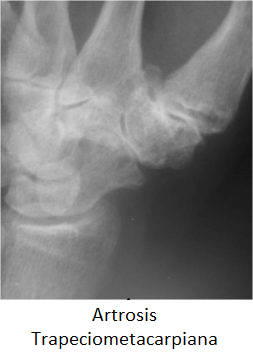

• La prueba de Finkelstein (aducción pasiva del pulgar y desviación cubital de la muñeca) o la extensión del pulgar contra resistencia con la muñeca en desviación radial máxima reproducen los síntomas del paciente. Sin embargo, esta prueba también puede ser positiva en los pacientes con artrosis de la articulación trapeciometacarpiana y debe diferenciarse de este trastorno frecuente.

• Artrosis de la articulación trapecio metacarpiana (Rizartrosis)